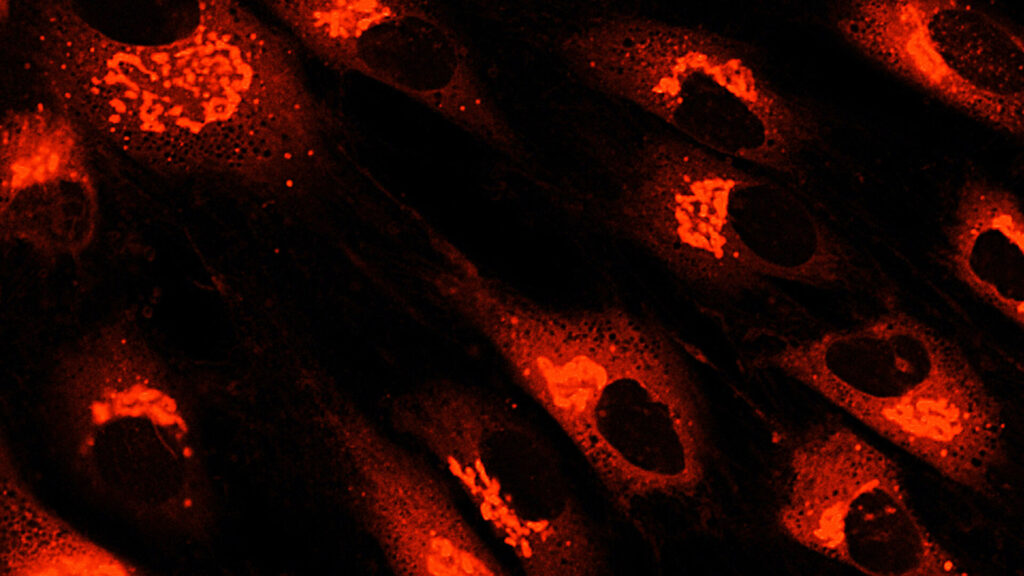

如今,MSC一詞描述了一類細胞,歷史上被稱為間充質(zhì)干細胞、間充質(zhì)基質(zhì)細胞和醫(yī)學信號細胞等。間充質(zhì)干細胞的臨床用途主要歸因于它們的關鍵生物學特性,其中包括:

根據(jù)臨床前和臨床證據(jù),間充質(zhì)干細胞治療免疫和炎癥性疾病顯示出特別的前景,研究人員正在探索間充質(zhì)干細胞衍生療法和外泌體在治療自身免疫性疾病、骨關節(jié)炎、炎癥性肝病、肺部疾病、移植排斥等方面的臨床應用。人們對同種異體間充質(zhì)干細胞的興趣也日益濃厚,因為它可以作為現(xiàn)成產(chǎn)品提供。

如今,間充質(zhì)干細胞正在新興應用中得到應用,例如組織工程、類器官、外泌體生產(chǎn)、藥妝品和培養(yǎng)肉。此外,人們正在探索iPSC衍生的MSC在MSC療法開發(fā)中的作用,因為這些MSC可以經(jīng)濟地以幾乎無限的規(guī)模批量生產(chǎn)。